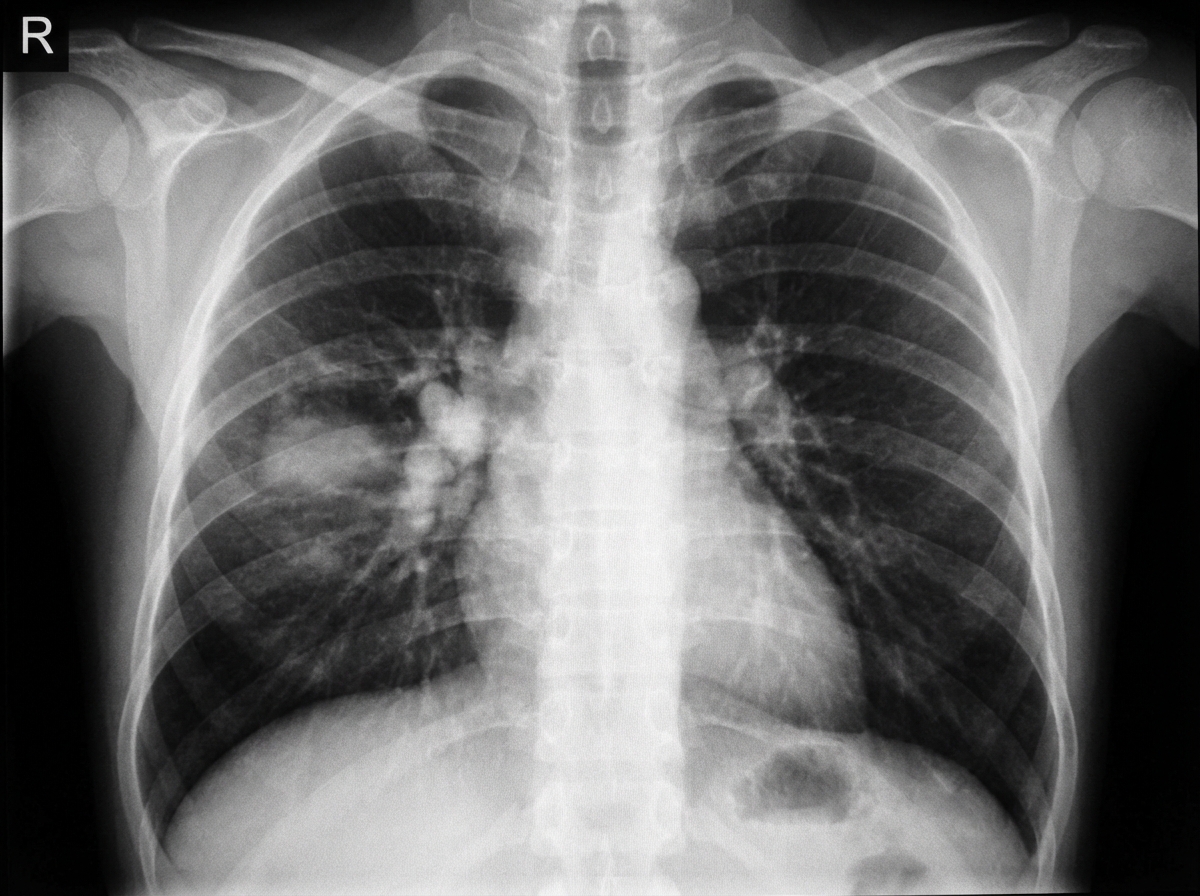

A 4-year-old child presented with cough persisting for 1 month and low-grade fever. There was a history of contact with TB. What is the chest X-ray suggestive of?

Explanation: ***Primary TB*** - A 4-year-old child with **TB contact** and persistent cough typically presents with **primary TB complex** (Ghon focus + hilar lymphadenopathy). - Primary TB in children characteristically shows **hilar lymphadenopathy** with or without parenchymal infiltrates, forming the **Ranke complex**. *Pleural effusion* - More commonly seen in **adolescents and adults** with post-primary TB, not typical in young children. - Would present with **decreased breath sounds** and **dullness to percussion**, which are not mentioned here. *Miliary TB* - Chest X-ray would show **diffuse tiny nodules** (2-3mm) throughout both lung fields, resembling millet seeds. - Represents **hematogenous dissemination** and typically presents with more severe systemic symptoms than described. *Cavitation* - A feature of **post-primary (adult-type) TB**, extremely rare in children under 10 years of age. - Occurs due to **caseous necrosis** and tissue breakdown, which is uncommon in primary TB due to immature immune response.